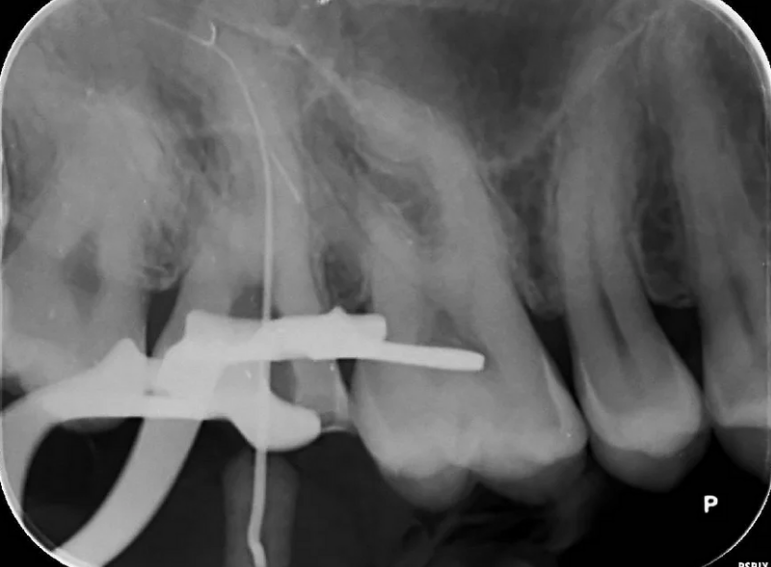

Separated instrument management on a sclerosed upper second molar.